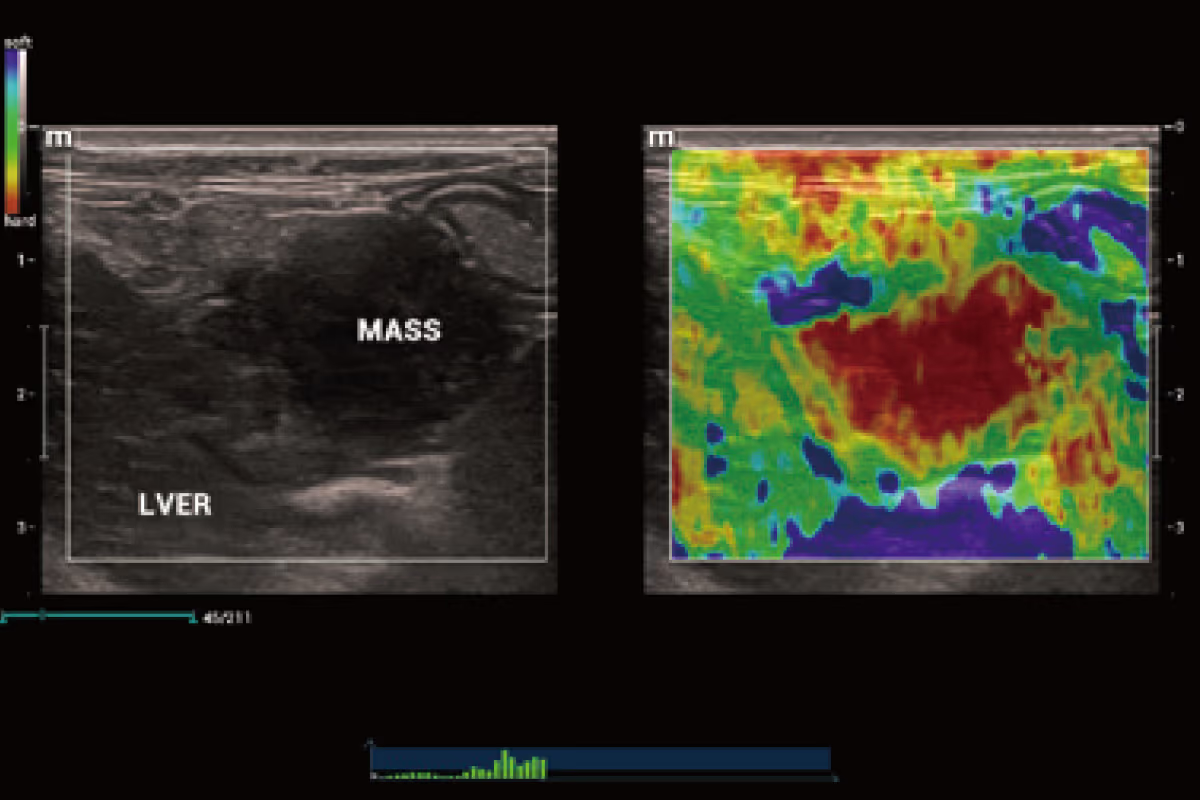

Mindray Animal Medical'ın patentli Natural Touch Elastografi teknolojisi, yumuşak dokuların elastik özellikleri ve sertliğinin doğru ve tekrarlanabilir bir değerlendirmesini sağlar.